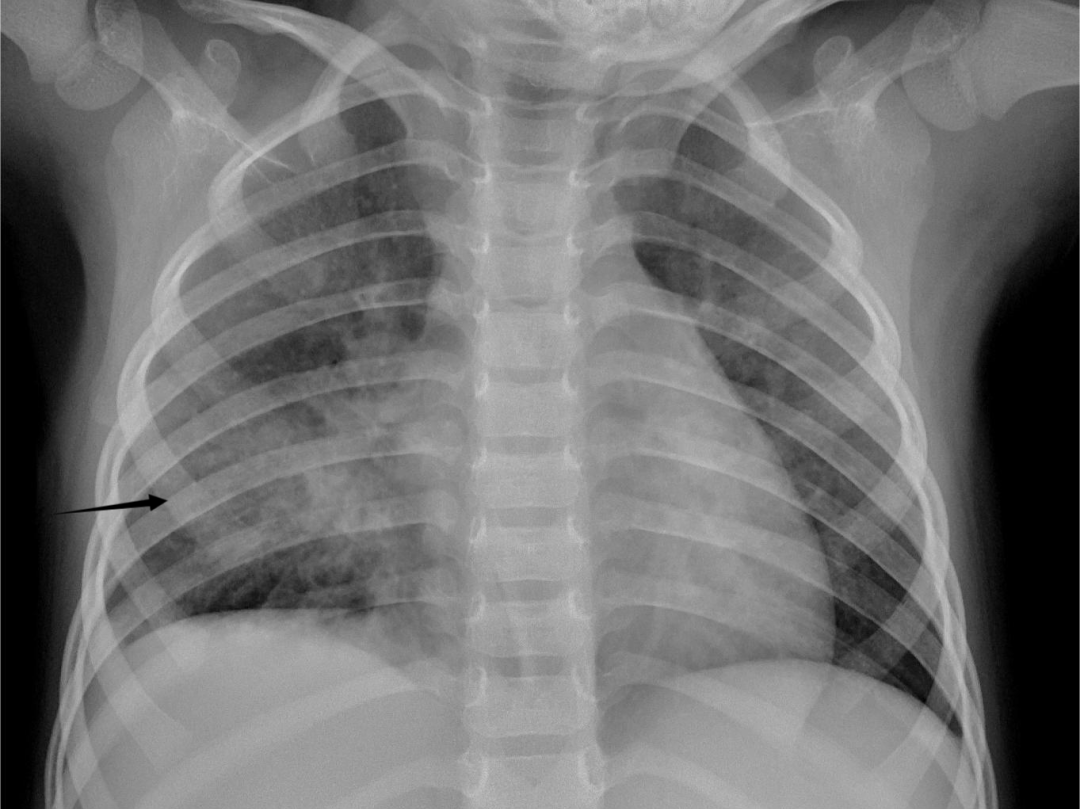

上图患儿发热咳嗽 6 天,无其他不适,外边诊所吃药无好转,来院拍片,如上图箭头所指,右肺肺炎。